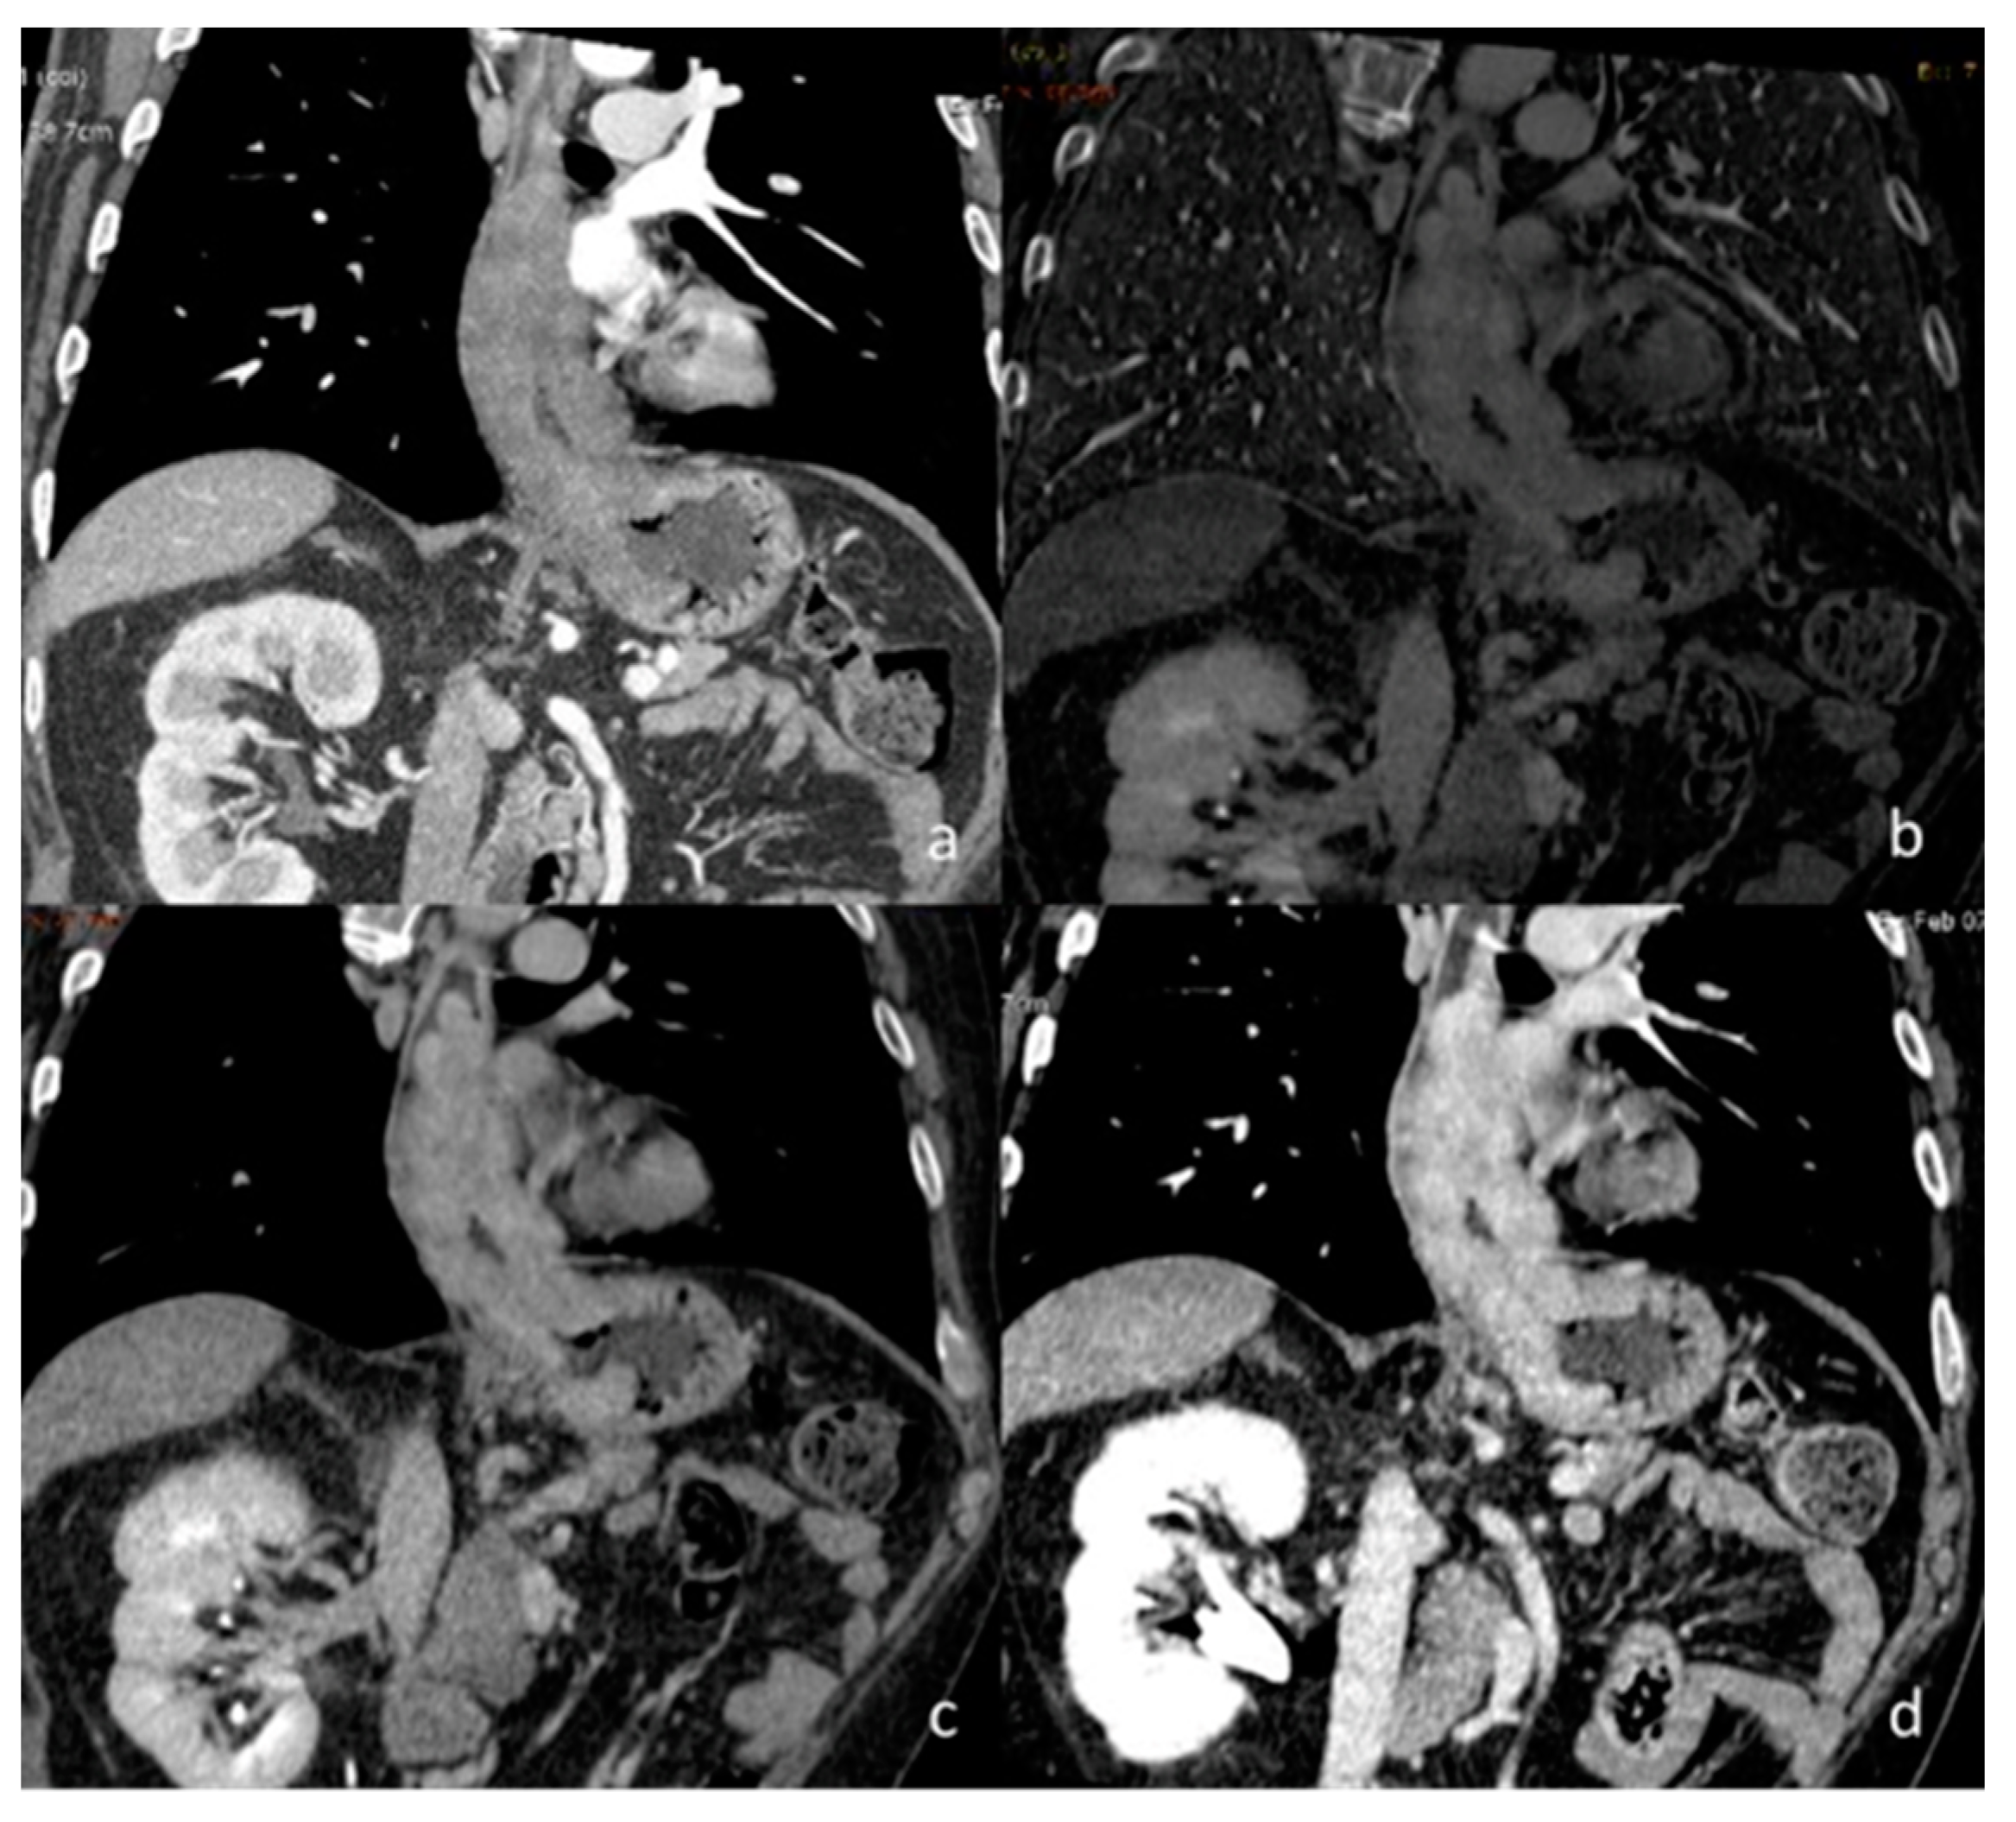

- Huang, F.; Wu, H.; Lai, Q.-Q.; Ke, X.-T. Application value of preoperative dual-source computed tomography in assessing the rupture site of thoracic aortic dissection. J. Cardiothorac. Surg. 2021, 16, 346. [Google Scholar] [CrossRef] [PubMed]